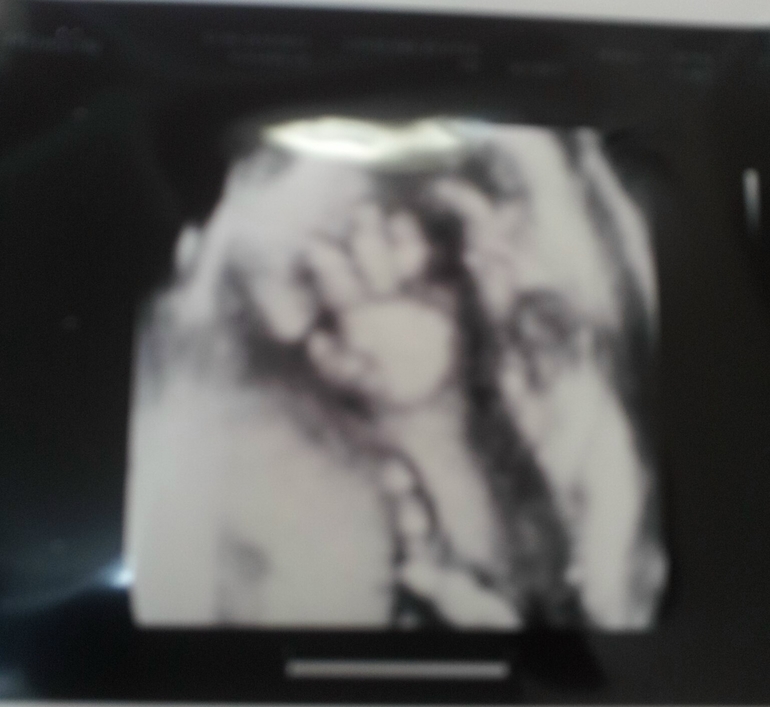

Наше 4 д узи на 30 неделе.

УЗИ, КТГ, доплерСходили мы на 4 д в 30 недель, эмоций море, как же это прекрасно!!!Всем огромное спасибо за советы, мы остались очень довольны результатом, Всем советую!!!Наше маленькое солнышко вел себя хорошо, порадовал папулю и мамулю.С самого начала он прикрывал свои сладкие губочки ручками, маме пришлось слегка покрутиться и мы были у цели.Какой же ты славный сыночек наш, пухленькие губки и щечки, носик картошечкой, так и хочется тебя расцеловать,мы тебя очень любим и ждем!!!Самое клевое это когда тетя угостила маму конфеточкой и сказала, сейчас начнется смотрите.Спустя пару минут рассасывания карамельки мы обомлели от восторга, наш сладкий карапузик начал причмокивать и заглатывать воды)))ми ми ми!!!Лежим мы как положено головкой вниз,умничка наш перевернулся , а потом решили глянуть наше достоинство, краник от нас сегодня скрыли, но зато какие у нас абрикосыыыыыы, (огромные))))100 % мужичек!!!В итоге результатом узи мы очень довольны, нам дали 9 фото и диск с записью 20 минут видео